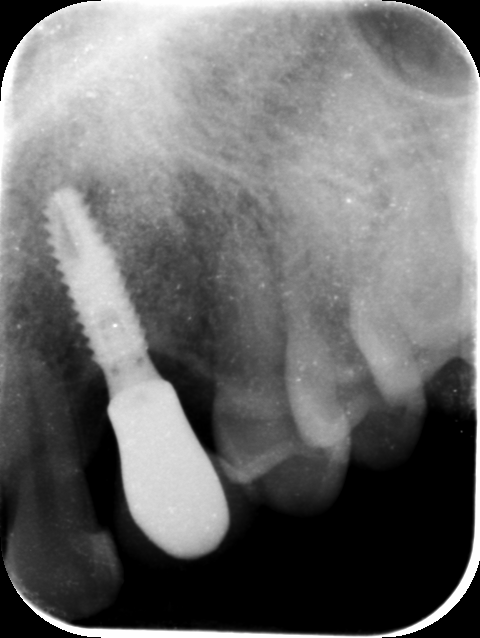

do you recognize this IMZ implant? it was used in 1991. i don't know how to find a replacement for this screw attached a picture of the part x-ray [...]